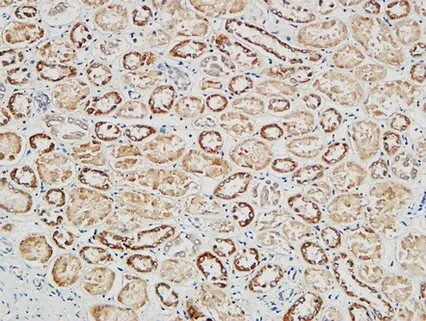

Glut4 Rabbit Polyclonal Antibody

Cat: APRab11504

Size1:50μl Price1:$118

Size2:100μl Price2:$220

Size3:500μl Price3:$980